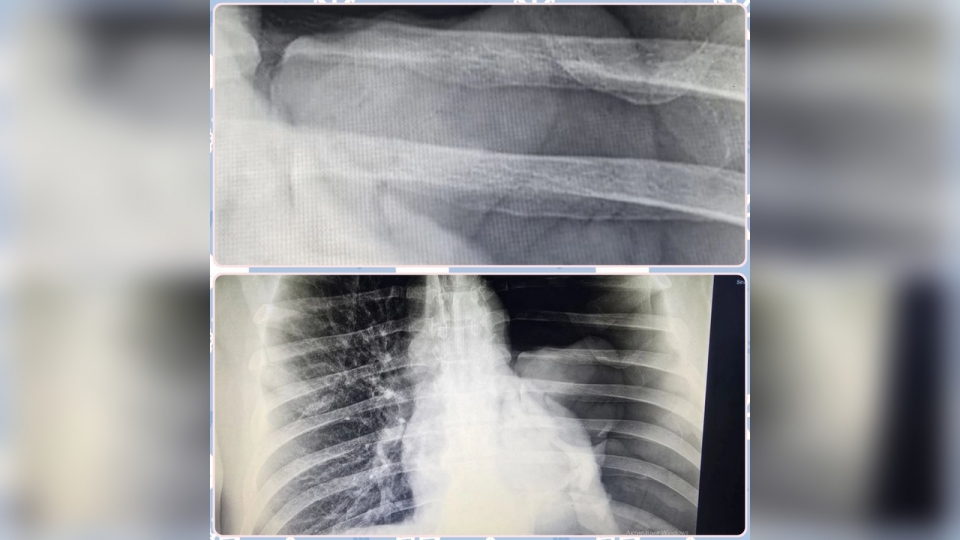

Один из пациентов, 49-летний житель Маянги, упал с двухметровой высоты, но обратился за помощью только через три дня, когда боль и одышка стали невыносимыми, рассказал заведующий травматологическим отделением Алексей Засенцев. Диагноз – напряженный пневмоторакс: левое легкое полностью "сдулось". Хирурги экстренно установили дренаж, пациента спасли.

В Широком Буераке 69-летний мужчина при падении в гараже получил обширную рваную рану грудной стенки с отрывом большой грудной мышцы и переломом ребер. Его экстренно прооперировали под общим наркозом.